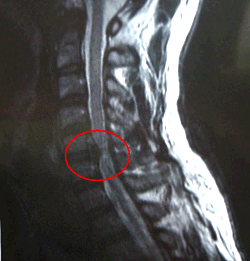

■首の骨側面

首の骨5番と6番の所にヘルニアが見られます。